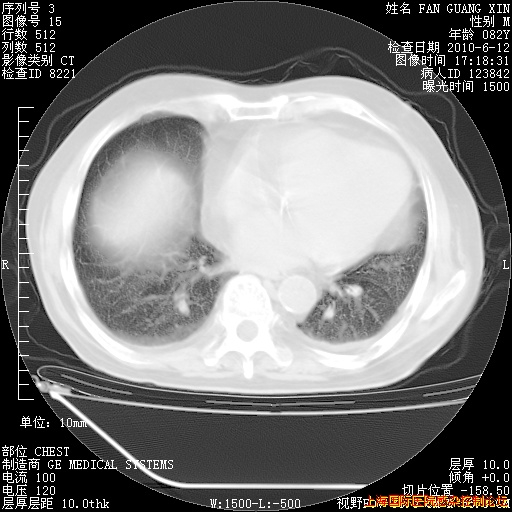

补发6月12日肺部CT肺窗

回复

6月12日肺窗